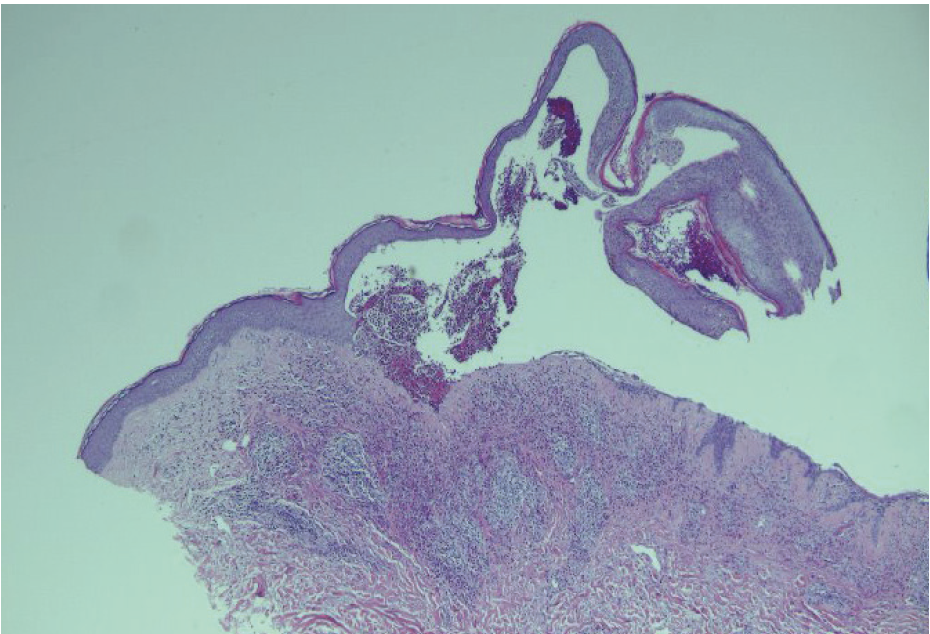

The patient’s diagnosis of localized BP was confirmed with H&E stain and DIF histopathology, which revealed eosinophil-rich subepidermal blistering and a linear deposition of IgG and C3 along the basement membrane, respectively (Figures 2–4). Serology was also positive for BP180 antibodies. The patient was prescribed topical clobetasol propionate 5% cream, which led to significant improvement in his pruritus and bullae. He denied systemic therapy and is being closely monitored. To date, the patient has not experienced any recurrence or disease progression.

Histopathology will reveal a clean split at the dermoepidermal junction and formation of a subepidermal blister with eosinophils. Direct immunofluorescence (DIF) is considered the gold standard for diagnosis and will reveal linear IgG and/or C3 at the basement membrane in nearly 100% of cases. Serologic workup will be positive for autoantibodies against BP180 or BP230.2